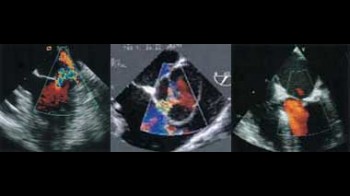

• transtorakalnu ehokardiografiju